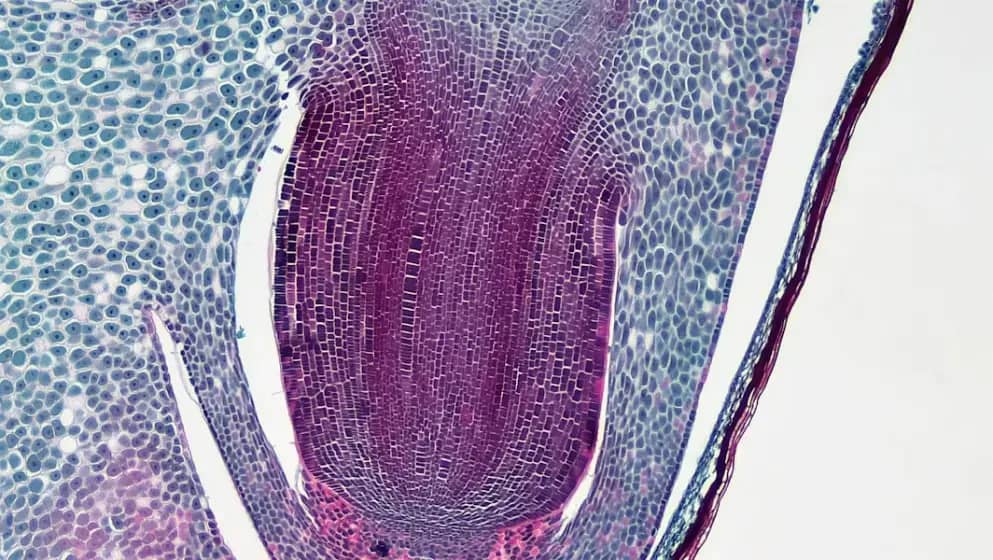

Larve parazita se nalaze u mesu zaraženih divljih i domaćih životinja. Čovek može da se zarazi konzumacijom nedovoljno termički obrađenog mesa. Glavni izvor zaraze je svinjsko meso zaraženih svinja.

Nakon klanja svinja, nužno je uraditi trihineloskopski pregled mesa. Osobe sa simptomima trihineloze trebaju se odmah javiti lekaru, dok je preporučljivo da se i oni koji su konzumirali zaraženo meso jave na pregled.